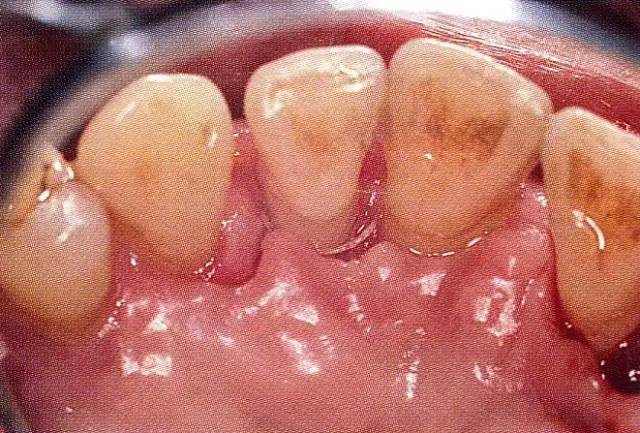

案例3   針對3壁性垂直性骨缺損使用非吸收性膜進(jìn)行再生治療,再翻瓣時進(jìn)行骨形態(tài)修整的病例。

▲圖7-1  左下6近中可觀察到3壁性垂直性骨缺損。此病例考慮到齦瓣供血關(guān)系,在前磨牙部位進(jìn)行了減張切開,沒有進(jìn)行縱切開。并利用刮治器、牙周外科用車針進(jìn)行了徹底的骨缺損部位搔刮。